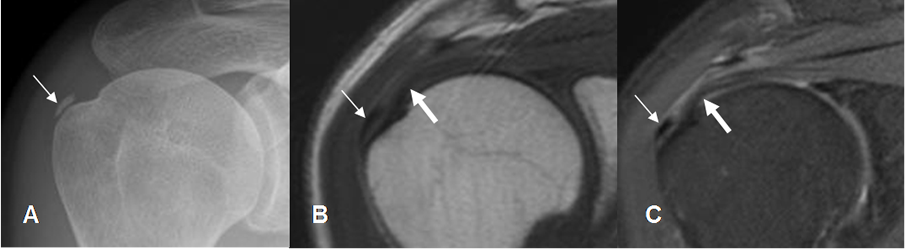

Fig 144. Bursitis subdeltoidea crónica.

A: Rx AP. Calcificación gruesa por encima de la tuberosidad mayor, por tendinitis o bursitis crónica.

B: RM coronal en T1 y C: RM coronal en STIR. Ausencia de señal por calcificación gruesa (Flecha delgada), por encima del tendón del supraespinoso el cual conserva su señal. (Flecha gruesa). Los cambios son compatibles con bursitis crónica.